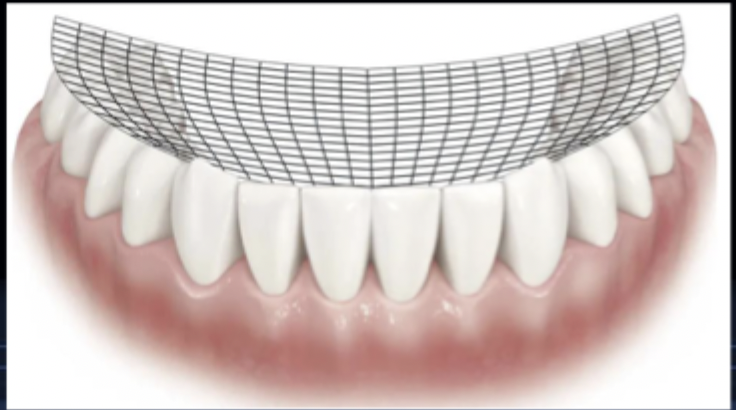

small shift from CO to MI (grinding motion)

what is the curve of spee?

the curvature which begins at the tip of the canines and follows the buccal cusps of the posterior teeth, when viewed from the facial; continues up the arch through the condyle

<p>the curvature which begins at the tip of the canines and follows the buccal cusps of the posterior teeth, when viewed from the facial; continues up the arch through the condyle</p>

New cards

what is the curve of wilson?

mediolateral curvature of the occlusal plane of posterior teeth

<p>mediolateral curvature of the occlusal plane of posterior teeth</p>

what is the curve of monson (also known as sphere of Monson)?

three-dimensional curvature of the occlusal plane, which is a combination of the curve of spee and curve of wilson

<p>three-dimensional curvature of the occlusal plane, which is a combination of the curve of spee and curve of wilson</p>